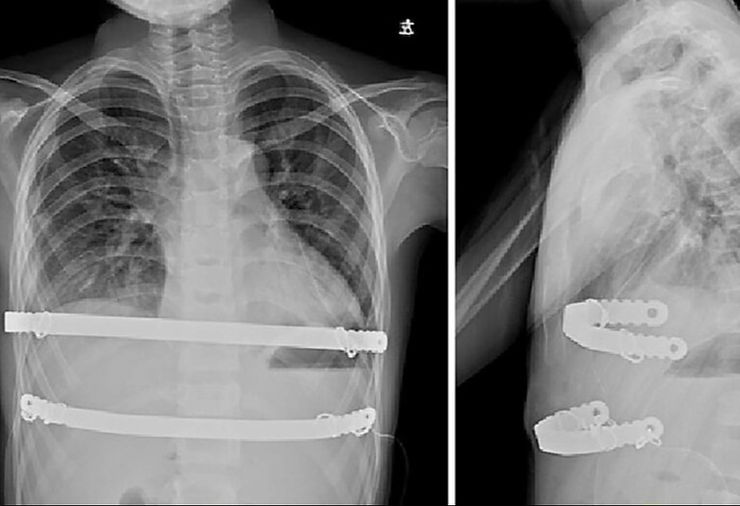

Bars implanted inside the body during the Nuss procedure.

Extensive clinical practice shows that the bars inside the body usually do not cause discomfort to patients, and most patients are hardly aware of their presence.